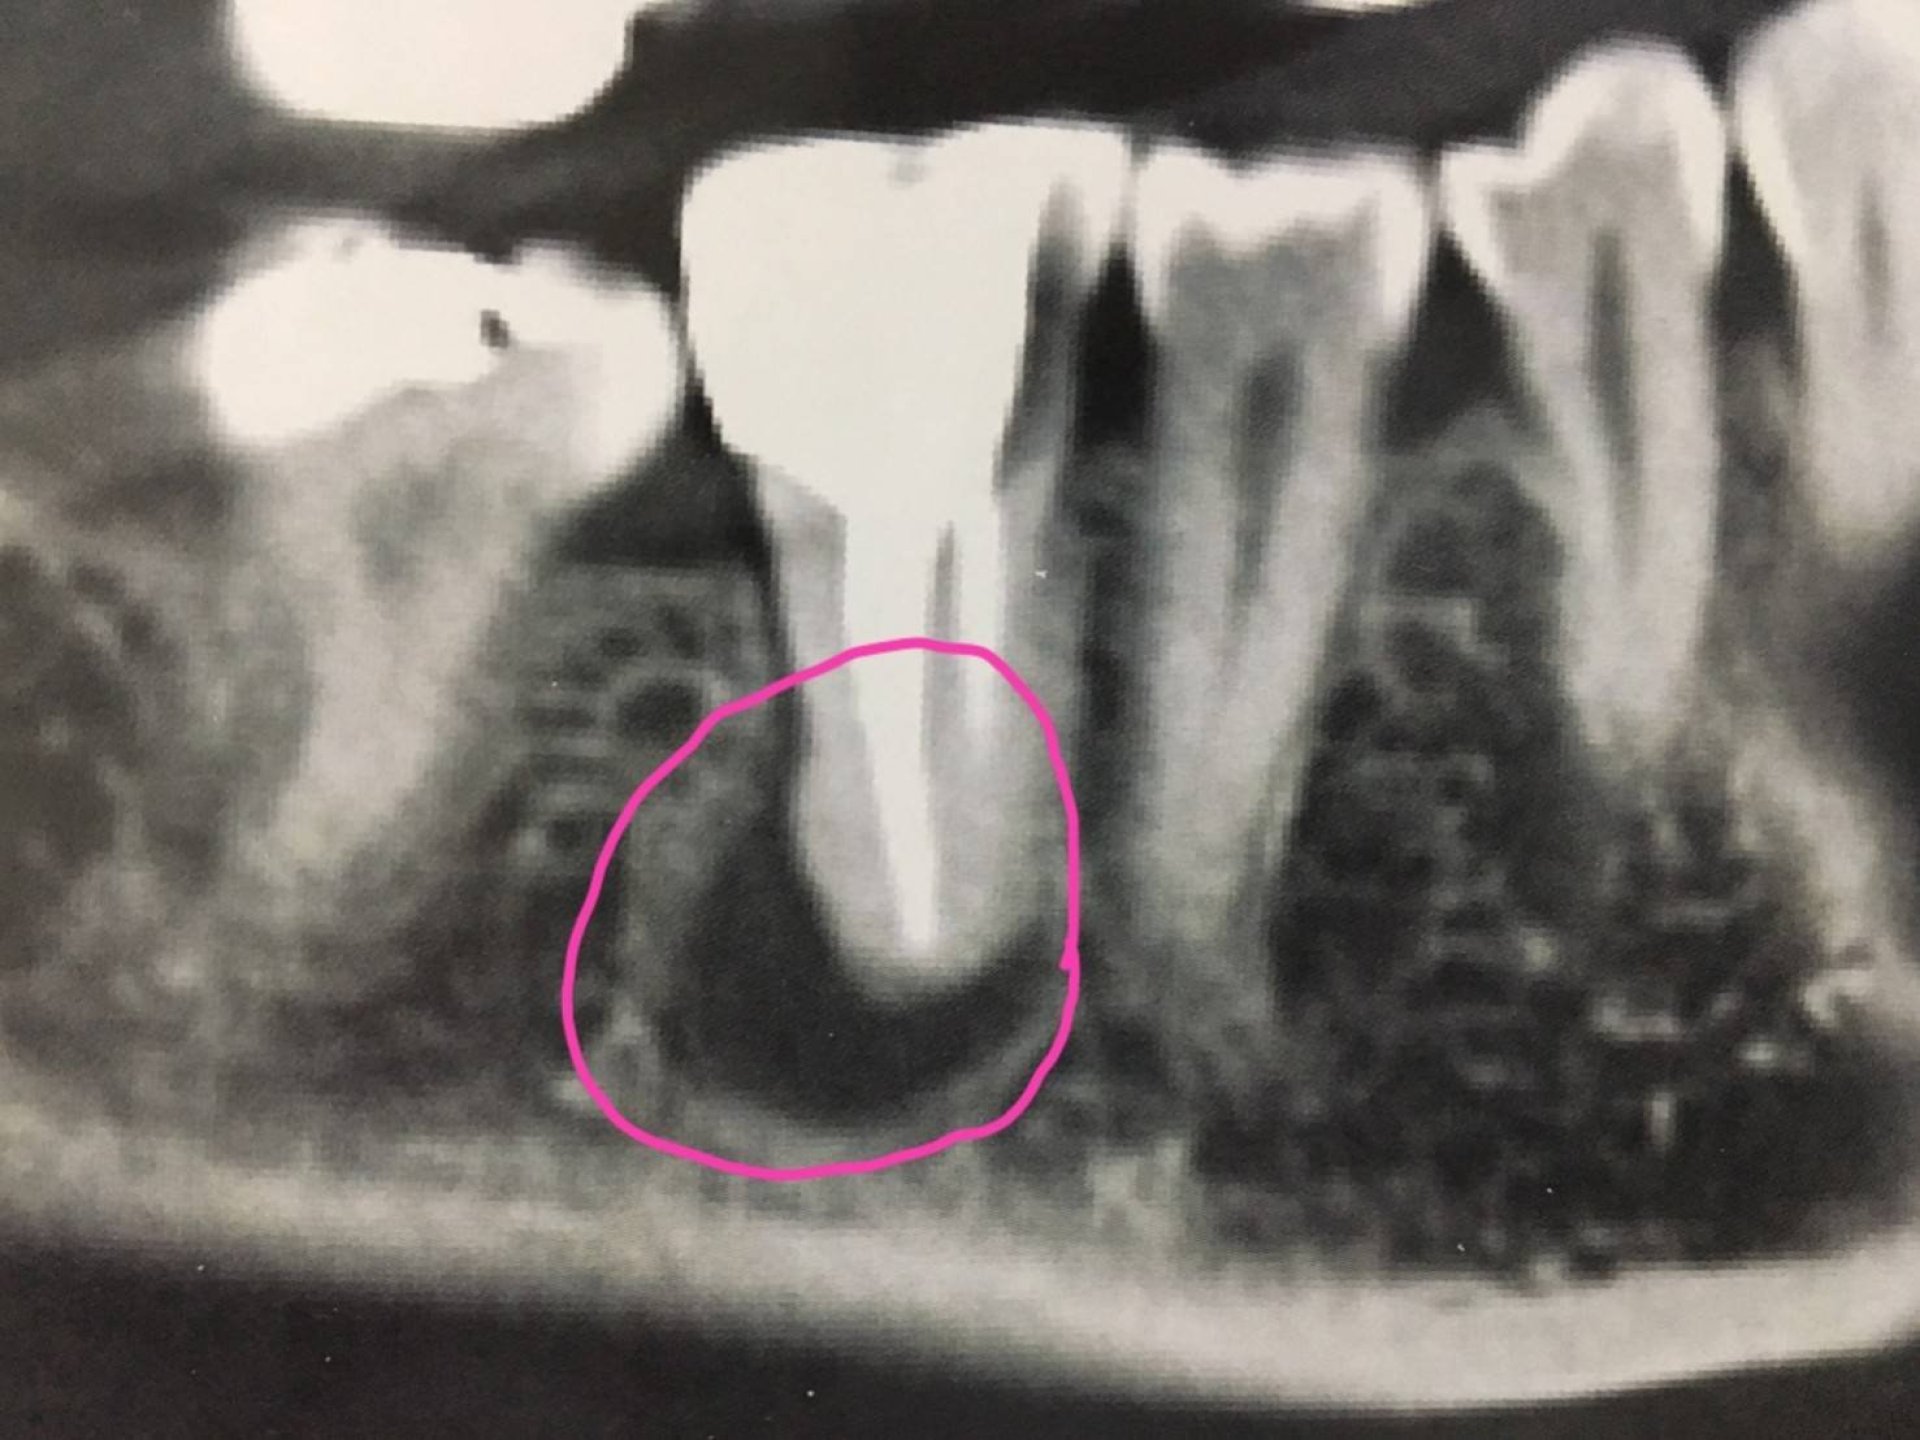

บริเวณสีดำในวงสีชมพู คือ กระดูกรองรับรากฟัน ที่เป็นโพรง เนื่องจากการรักษารากฟันไม่เป็นผลสำเร็จ จึงต้องถอนฟันซี่ดังกล่าวเมื่อปลาย มิย. 2560 เพื่อรอให้กระดูกรองรับรากฟัน มีการสร้างขึ้นมาใหม่ (ถมโพรงให้ตื้นขึ้นมา) เพื่อให้มีเนื้อที่กระดูกเพียงพอสำหรับการใส่รากฟันเทียม

วันนี้ครบ 2 เดือน คุณหมอเอ็กซเรย์ พบว่า โพรงกระดูกรองรับรากฟัน ตื้นขึ้นมาก เกือบเต็ม จึงจะผ่าเปิดดูกระดูกรองรับรากฟัน โดยมี 3 ทางเลือก